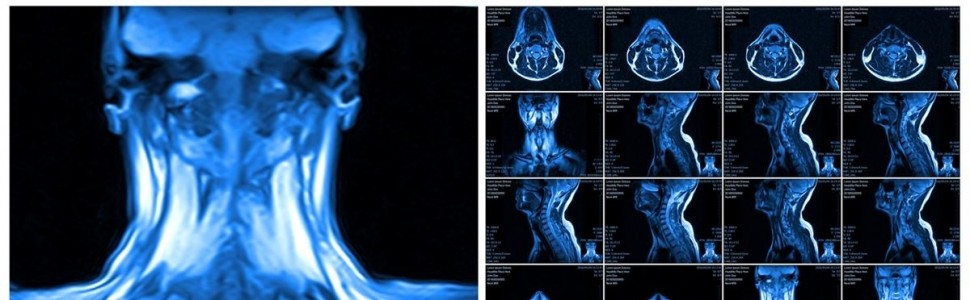

Coraz częściej pacjenci przychodzą do gabinetu stomatologicznego w celu zdjęcia retainera lub stałego aparatu ortodontycznego, gdyż odmówiono im wykonania badania rezonansu magnetycznego z tymi aparatami. Czy radiolodzy mają rację, każąc pacjentom zdejmować aparat?

W związku z tym, że leczenie ortodontyczne staje się coraz powszechniejsze, także wśród dorosłych, rośnie grupa osób użytkujących aparaty ortodontyczne stałe oraz retainery. Dlatego coraz częściej w pracowniach tomografii magnetycznego rezonansu jądrowego (potocznie zwanego rezonansem magnetycznym, MR) pojawiają się pacjenci w trakcie leczenia ortodontycznego lub po jego zakończeniu. O ile zdjęcie i ponowne założenie retainera nie jest jeszcze tak kosztowne (słyszałam, że część ortodontów w sytuacji przymusowego zdjęcia retainera oferuje ceny promocyjne), to naklejenie nowych zamków aparatu stałego wiąże się już z wysokim kosztem. Nie wszystkie badania MR można odsunąć w czasie na okres po zakończeniu leczenia ortodontycznego. W związku z licznymi zapytaniami w tej sprawie ze strony lekarzy dentystów z całej Polski Polskie Towarzystwo Stomatologiczne, Polskie Towarzystwo Ortodontyczne i Polskie Lekarskie Towarzystwo Radiologiczne powołały zespół roboczy* w celu opracowania schematu postępowania z pacjentami z aparatami ortodontycznymi, u których wykonywane są badania MR.

3. Jeśli nawet aparat ortodontyczny czy retainer nie jest wykonany ze stopów o właściwościach ferromagnetycznych, to i tak w badaniu MR metale powodują powstanie artefaktów o różnym nasileniu, które są ograniczone do okolicy głowy. Jeżeli są badane inne okolice ciała pacjenta, artefakty te nie obniżają jakości obrazu. Ponadto istnieją techniczne możliwości redukcji artefaktów przez unikanie niektórych sekwencji akwizycji obrazu i/lub zastosowanie obrazowania w innych płaszczyznach.